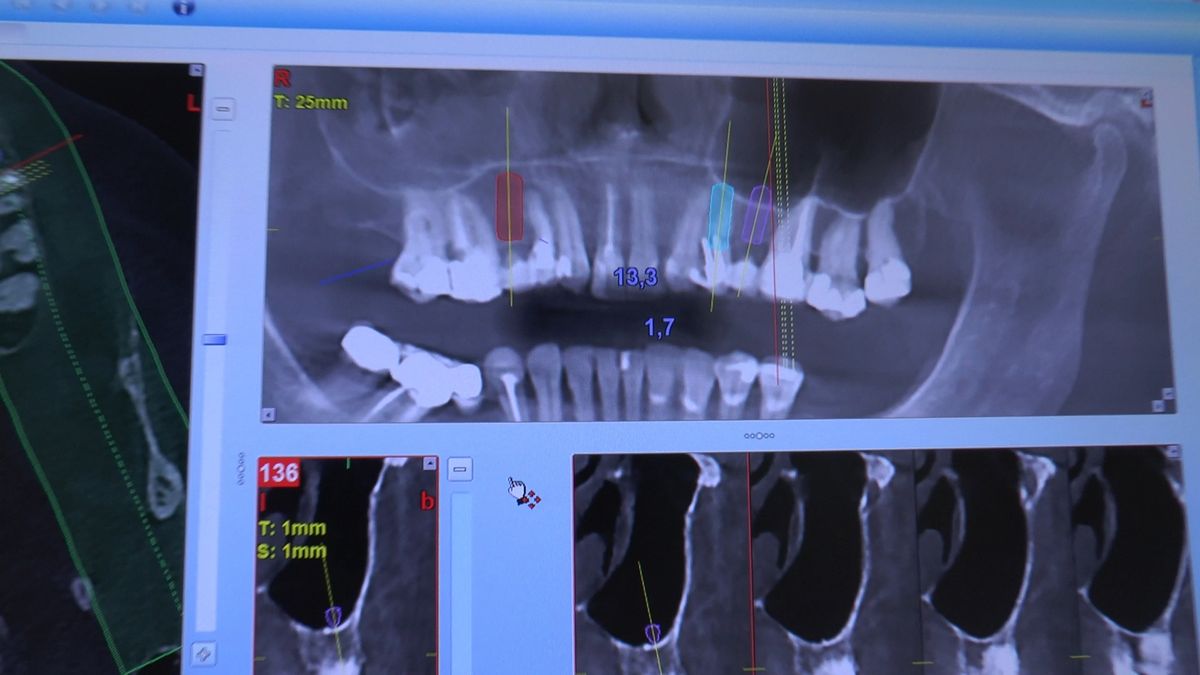

W ostatni weekend czerwca 2018 roku kursanci II Sezonu Preludium Implantologii odbyli piątą, finałową sesję, która w całości podporządkowana była praktyce. W ciągu dwóch dni zabiegowych Lekarze uczestniczący w szkoleniu przeprowadzili szereg zabiegów pod kierunkiem dr n.med. Violetty Szycik. Wszczepili 17 implantów oraz przeprowadzili ekstrakcje i zabiegi regeneracyjne kości. Zabiegi były wykonywane także w sedacji dożylnej z udziałem specjalisty anestezjologii i intensywnej terapii dr Jolanty Grzybowskiej. Preludium implantologii to nowy program edukacyjny dla adeptów implantologii stomatologicznej, którego celem jest wprowadzenie do implantologii poprzez pozyskanie wiedzy w szerokim zakresie i uwzględnieniem szczegółów mających decydujące znaczenie dla powodzenia leczenia implantologicznego. Ale tak jak wszystkie szkolenia w Instytucie Vivadental, w tym wiodące Practiculum Implantologii, zorientowane jest na praktyce i samodzielnym wykonywaniu zabiegów pod kierunkiem Mentora. To najlepsza edukacja w medycynie zabiegowej, a zarazem najlepszy start do implantologii.